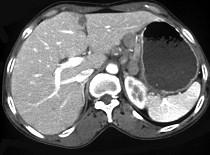

问题 女,56岁,上腹部钝痛、腹胀不适1月余,纳差、消瘦,影像检查如图,最可能的诊断是 ( )

选项 A.胃幽门管溃疡 B.胃腺癌并幽门狭窄 C.胃淋巴瘤 D.胃间质瘤 E.胃恶性间质瘤

答案 B